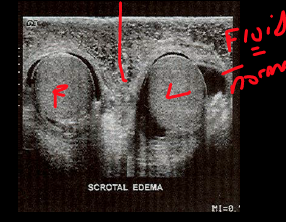

This type of tissue creates a____ in the scrotum or_____ within the abd. of pleural fluid within the thorax.

hydrocele, ascites

what can you see here? why?

Scrotal wall is inflamed but the median raphe is clearly seen separating the two hemiscrotums.